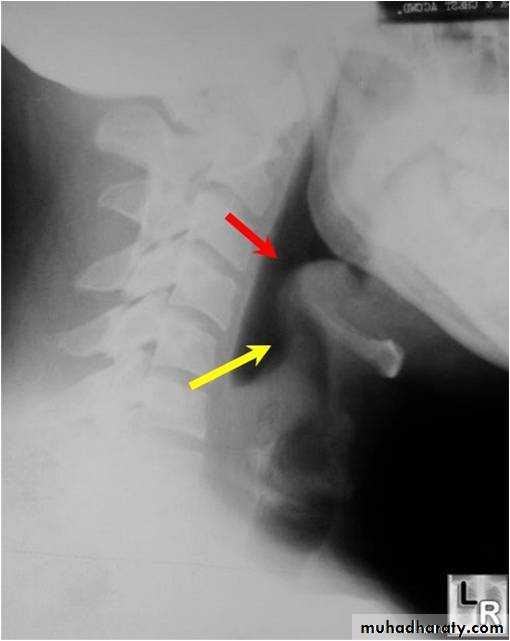

• 1. chest radiography must always be taken when there is persistent laryngeal symptoms from any cause to exclude TB of the lung